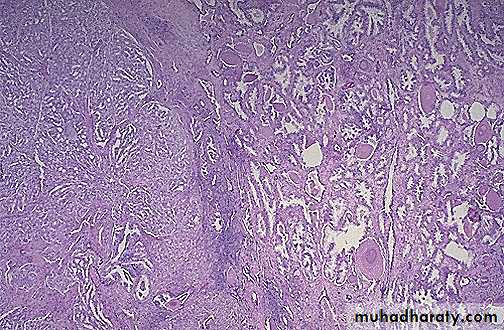

At the right are normal prostatic glands containing scattered corpora amylacea. At the left is prostatic adenocarcinoma. Note how the glands of the carcinoma are small and crowded.